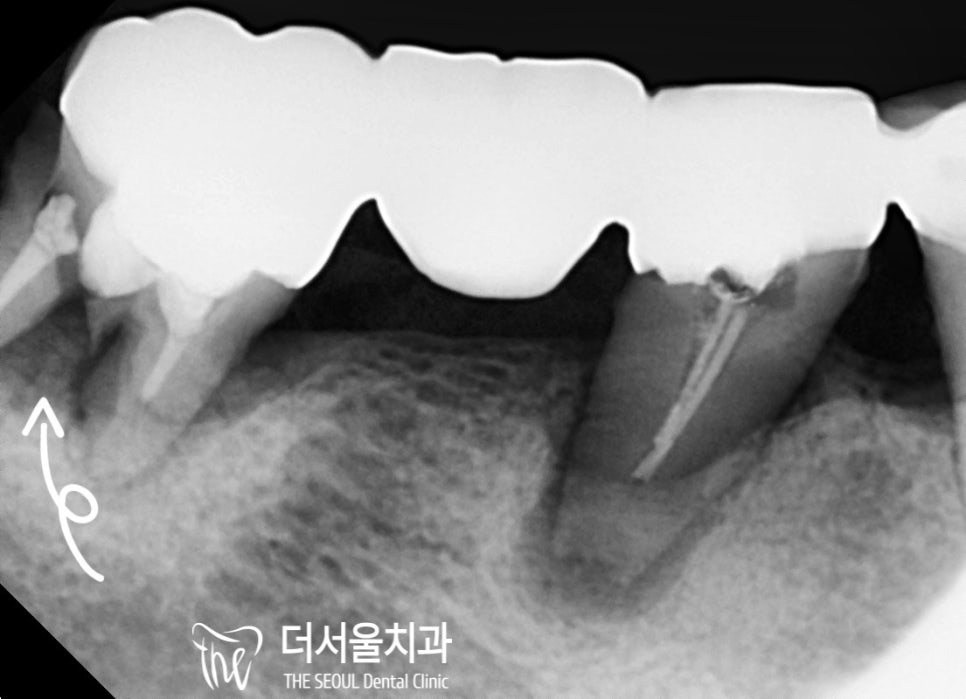

엑스레이 촬영을 통해 좀 더 자세히 살펴보니

빠져버린 치아 말고도 여러 문제들이 관찰되었습니다.

1) 곳곳에 심한 골소실

2) 대합치 정출

3) 심한 동요

자, 우선 왼쪽 뼈이식 임플란트 를 진행해야 되는 데…

오른쪽 상황이 꽤 좋지 않았습니다.

조금만 아차 하면 자연 발치로 이어질 것 같았는데요.